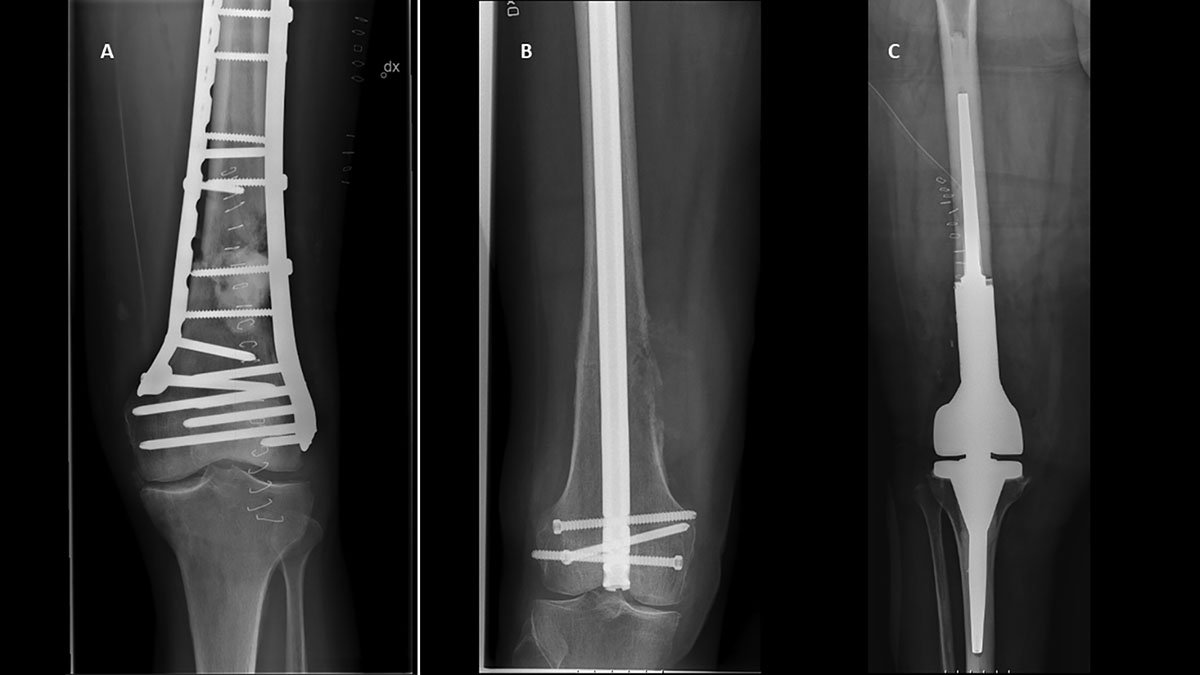

Representative cases of patients who underwent surgical treatment with distal femoral metastases. A. Plate osteosynthesis for lung cancer metastasis with displaced pathological fracture B. Retrograde nail osteosynthesis for colon cancer metastasis with non-displaced pathological fracture C. En bloc resection and megaprosthesis reconstruction for renal cancer metastasis with displaced pathological fracture.